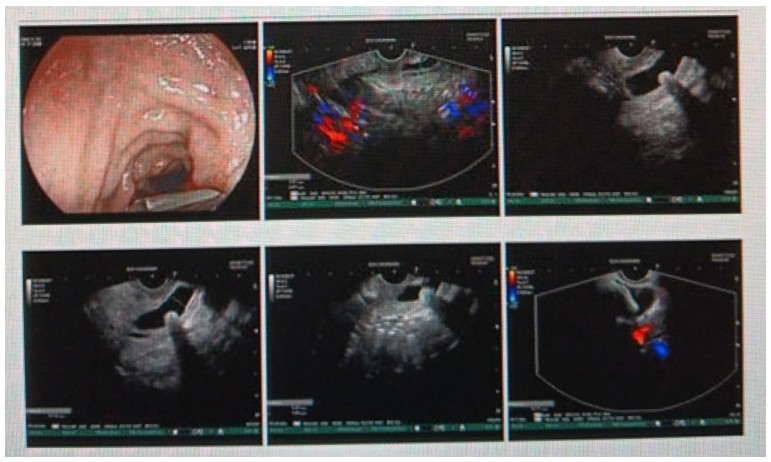

消化內(nèi)科肝病亞??茍F(tuán)隊(duì)詳細(xì)討論,分析患者情況后,取消了周女士的肝穿刺活檢檢查,建議患者先行超聲胃鏡下膽胰掃查。在內(nèi)鏡醫(yī)師第三只眼——超聲胃鏡的掃查下,發(fā)現(xiàn)引起周女士肝功能受損的罪魁禍?zhǔn)?/span>原來是膽總管末端結(jié)石!伍友興主任醫(yī)師帶領(lǐng)團(tuán)隊(duì)給予患者行ERCP下取石后,周女士未再出現(xiàn)腹痛,肝功能恢復(fù)正常。

無獨(dú)有偶,劉先生也為反復(fù)出現(xiàn)肝功能受損到多家醫(yī)院就診檢查,未能找到原因,來到衡陽市中心醫(yī)院消化內(nèi)科就診,希望能在肝穿刺活檢下得出病因。在行肝穿刺活檢之前,醫(yī)生建議劉先生行超聲胃鏡膽胰掃查,發(fā)現(xiàn)引起劉先生反復(fù)肝功能受損原因,亦是膽總管結(jié)石引起,在ERCP術(shù)取石術(shù)后,患者肝功能恢復(fù)正常,未再出現(xiàn)異常情況。

張丹霞主任醫(yī)師介紹,超聲內(nèi)鏡通過胃十二指腸自然腔道,可以將探頭貼近相應(yīng)的位置,近距離的觀察胰腺及膽道系統(tǒng),準(zhǔn)確捕捉到直徑小于5毫米的胰腺異常病灶及膽道系統(tǒng)病灶。而體表B超常受皮膚、脂肪或腸道氣體干擾。CT或磁共振檢查只能提供靜態(tài)圖像,且對(duì)膽胰管陰性結(jié)石或是未引起明顯膽管梗阻性的結(jié)石檢查有局限性,因此對(duì)于有輕微腹痛合并肝功能受損的患者,建議常規(guī)行超聲胃鏡下膽胰掃查。超聲胃鏡、腹部彩超、腹部CT、腹部MRI同為診斷膽管細(xì)微病變的四架馬車,在膽總管結(jié)石診斷方面,超聲胃鏡膽胰掃查同ERCP一樣,是敏感性高、特異性強(qiáng)的診斷方法。超聲胃鏡發(fā)現(xiàn)可疑病變,可以完成穿刺活檢,還可行囊腫穿刺引流、膽管減壓、消融術(shù)等。